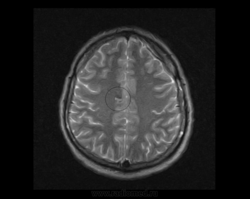

М, 27 лет. Жалобы на головные боли. ЧМТ в анамнезе. Стационар выставил внутримозговую гематому по КТ, полечили, отпустили.  К нам пришел на контроль.

Локализация таламус, граница коркового/мозгового, похоже на множественные кавернозные ангиомы. То, что в левой лобной?

Хочу посоветоваться с коллегами).  Дифференциальный ряд построить. Например токсоплазмоз, метастазы....в общем жду.

Сложно представить у молодого человека и каверномы, и метастазы одновременно.

Наверное, все же множественные каверномы, слева -осложненная кровоизлиянием.

Пришел к выводу, что сдесь все таки не каврномы, а мелкоочаговые кровоизлияния (ДАП). Учитывая травму и пребывание после этого  пациента в коме.